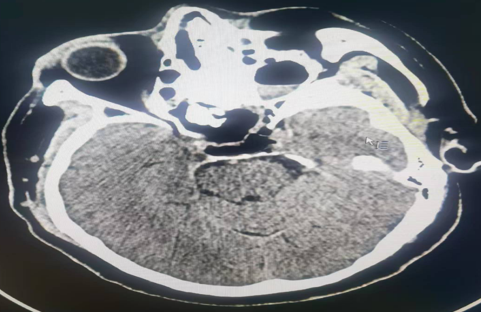

术后复查CT

肿瘤已彻底切除,无残留组织

之前“一粒大米”大小的垂体瘤

已长至“红枣”一般大30mm×19.6mm×27.7mm

体积大幅增大,不仅突破鞍隔进入鞍上池

形成了典型的“雪人征”

还压迫到了视交叉和左侧海绵窦

这也是他视力下降头痛、血压不稳的根本原因